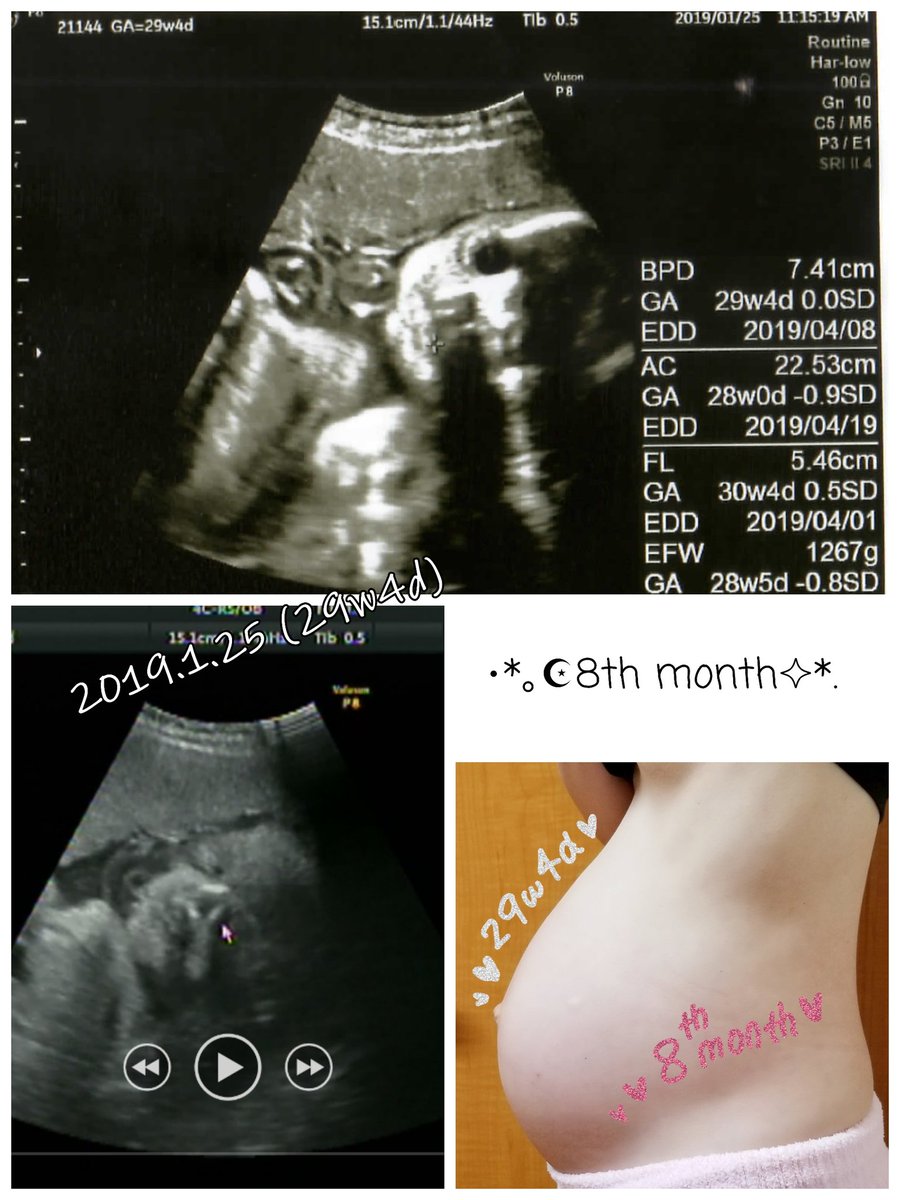

2019.1.25 すくすく成長してくれてるのが本当にありがたい。エコーでももう完全に人間が写ってて可愛いです。 エコーとお腹の写真載せます、閲覧注意! #育児漫画 #育児日記 #妊娠 #妊娠後期 #妊娠8ヶ月 #妊婦健診 #エコー #ママ垢さんと繋がりたい #オリジナル漫画 #絵描きさんと繫がりたい pic.twitter.com/kMN6lg0NRS

2019-09-01 11:41:52 拡大

拡大

拡大

拡大